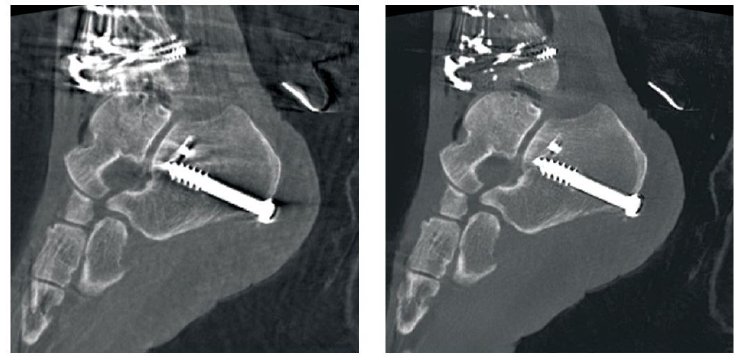

Ziehm Iterative Reconstruction (ZIR) for 3D systems

ZIR brings iterative reconstruction techniques – previously limited to CT scanners – to Ziehm Imaging's mobile 3D C-arms, automatically decreasing fan-beam and metal artifacts, resulting in a more distinguishable anatomy and easily defined bone crests. This, in turn, enhances volume rendering greatly, without increasing dose, which is especially important for complex orthopedic and vascular procedures.